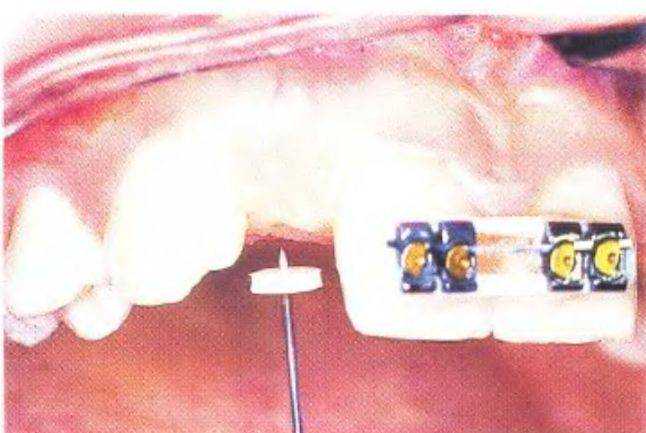

На первом этапе устранили диастему между верхними центральными резцами, чтобы создать пространство в области боковых резцов для установки имплантатов, что выполнили с помощью ортодонтического лечения (рис. с 3-39f по 3-39i). Прицельные рентгенограммы показали достаточное увеличение пространства (рис. 3-39j и 3-39к). Расстояние между верхушками корней можно было увеличить еще больше при использовании ретракционной проволочной дуги с петлями. Следует обсудить с ортодонтом варианты ортодонтического лечения. При проведении рентгенологической диагностики не следует соблюдать рекомендованный производителем оборудования протокол - необходимо подобрать параметры, которые используются при параллельном расположении зуба относительно пленки. Это позволяет полностью отобразить протрузионную и ретрузионную плоскости одновременно. Сотрудники стоматологической клиники, проводящие рентгенологическую диагностику, должны владеть этой методикой.

Рис. 3-39f. Устранение диастемы с помощью ортодонтического аппарата